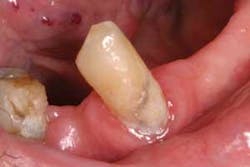

Pathogenesis: Normally, the clinical sign of a factitial injury is one in which the patient has produced an ulceration, hard tissue damage, or trauma to any tissue. In this case, the appliance is to blame. Mr. Saunders was aware of the missing teeth and the unstable position of the appliance, but he continued to wear the appliance. He was not aware that the appliance could become imbedded in tissue, but as time has progressed, the end of the metal appliance clasp has continued to become worn and even somewhat pointed (Figures 2 and 3).

Treatment and prognosis: A new appliance is greatly needed for this patient. Although the appliance has continued to fit the dentition, it has become more mobile with time and easily dislodged. The patient also exhibits poor oral hygiene and this may have caused the loss of previous dentition in this area (Figure 4).

The oral hygiene of the patient should be improved before a new appliance is made and the patient should be fully evaluated for periodontal disease. Radiographs should be taken and the patient may need close monitoring to form new habits related to total health maintenance. Patients should be counseled about prosthetic appliances that do not properly fit, are rough, or jagged. The appliances should be repaired or replaced when in poor condition. Jagged crowns or those that are in danger of being dislodged should be removed, replaced, or repaired.